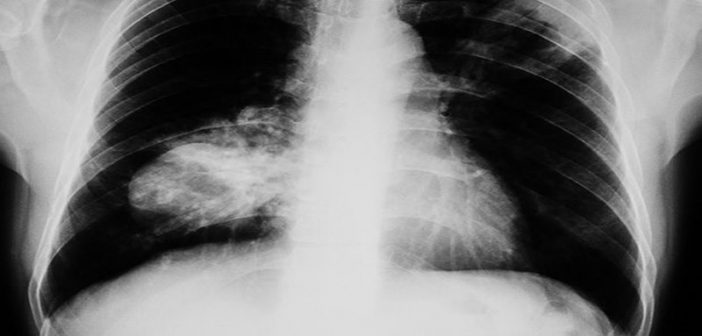

Le cancer du poumon non à petites cellules représente la majorité des cancers pulmonaires. Lorsqu’il est détecté assez tôt, il peut être opéré, mais près de la moitié des patients voient la maladie revenir malgré la chirurgie et la chimiothérapie. D’où la recherche de traitements plus efficaces avant et après l’opération.

L’étude internationale NeoCOAST-2 (phase II), à laquelle participe depuis 2022 l’Unité de Pneumo-Oncologie de notre établissement avec l’appui de l’Unité de Recherche Clinique, a permis à 9 patients de notre secteur d’accéder à une stratégie non encore disponible en soin courant, de chimiothérapie + immunothérapie avant la chirurgie (traitement « néoadjuvant »). Ils avaient ensuite accès à des associations innovantes telles qu’une double-immunothérapie ou une immunothérapie associée à un anticorps combiné à une molécule de chimiothérapie après la chirurgie (traitement « adjuvant »). Ces immunothérapies, dont le durvalumab systématiquement administré, sont des anticorps visant à libérer le système immunitaire contre les cellules cancéreuses.

Une 1ère analyse sur 202 patients traités, dont les résultats ont été publiés dans la revue scientifique de référence Nature, a conclu que l’un de ces traitements néoadjuvants, combinant durvalumab et un anticorps conjugué à un médicament appelé datopotamab deruxtecan (Dato-DXd), a permis d’obtenir une disparition complète de la tumeur chez 35 % des patients avant la chirurgie — un taux supérieur à celui observé avec les autres combinaisons testées.